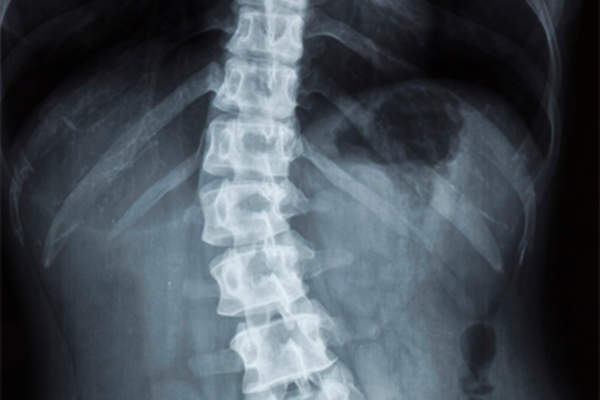

脊柱侧弯

脊柱侧弯脊椎弯曲度在10度或以上时被诊断约翰·霍普金斯大学医学院。有些人天生就有脊柱侧弯,而有些人成年后也会出现脊柱侧弯。患有脊柱侧凸的儿童通常不会感到背痛,而患有这种疾病的成年人通常以背痛为主诉。